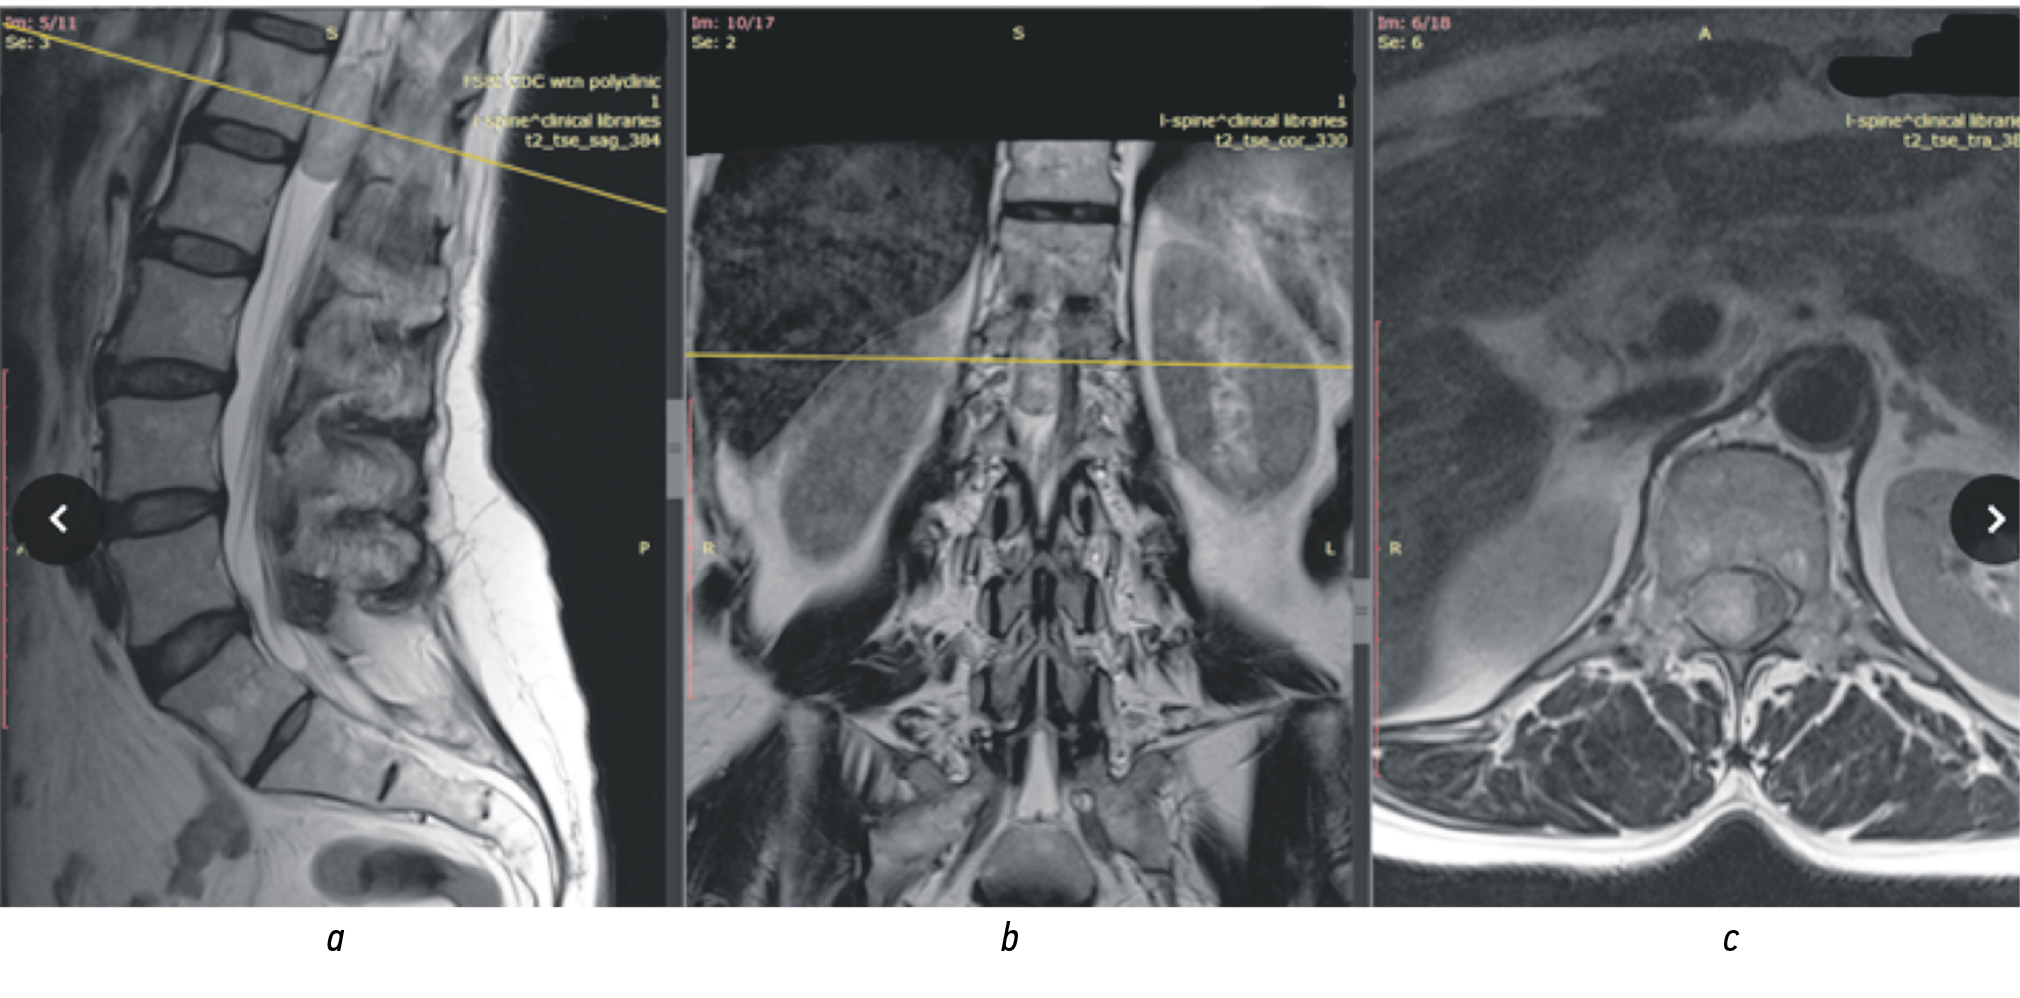

Клинический пример. Мужчина, 32 года. Диагноз: интрадуральная экстрамедуллярная шваннома на уровне L1 позвонка. Ведущим в клинической картине заболевания более 2,5 лет является болевой синдром в пояснично-крестцовом отделе позвоночника, нарастающий по интенсивности. Функция мочеиспускания пациента до операции была нормальной (4 балла по шкале NBSS). На МРТ пояснично-крестцового отдела позвоночника в просвете позвоночного канала на уровне LI–LIII позвонков парамедианно справа на уровне эпиконуса спинного мозга выявлено интрадурально-экстрамедуллярное объемное образование овальной формы с четкими ровными контурами размерами 32 × 15 × 16 мм (рис. 3).

Рис. 3. Магнитно-резонансная томограмма пояснично-крестцового отдела позвоночника: а — сагиттальная проекция; b — фронтальная проекция; с — аксиальная проекция. В просвете позвоночного канала на уровне LI–LIII позвонков парамедианно справа на уровне эпиконуса спинного мозга интрадурально-экстрамедуллярное объемное образование овальной формы с четкими ровными контурами размерами 32 × 15 × 16 мм

Fig. 3. Magnetic resonance imaging of the lumbosacral spine: a — sagittal projection; b — frontal projection; c — axial projection. In the lumen of the spinal canal at the LI–LIII LIII level, paramedially on the right at the level of the epiconus of the spinal cord, an intradural and extramedullary volumetric formation of oval shape with clear, even contours measuring 32 × 15 × 16 mm